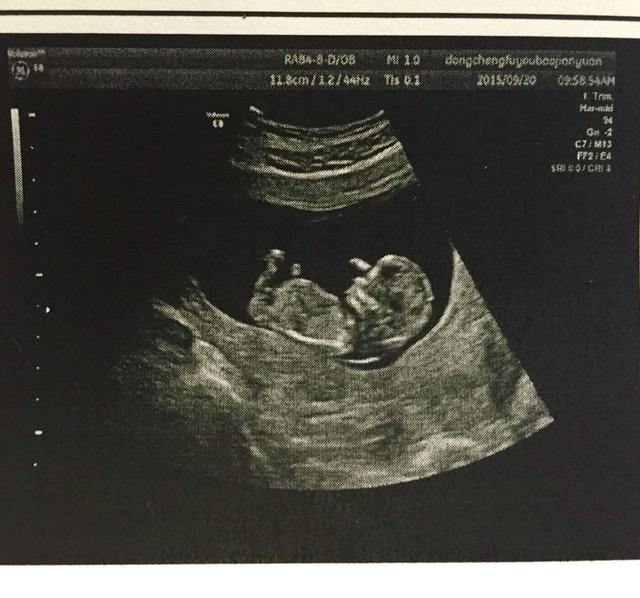

快到4个月的时分,去做B超产检,医生的一句话更让她们惊喜万分——双胞胎。但是随后一句话,让她接受不了,医生说有可能是连体婴儿。后面她基本没听到医生说些什么,就这样,她走出了B超室,在老公的陪伴下回家了。整天一泪洗面,想着各种结果,都不敢面对。

就在孩子分娩后的那霎时,当然一切人惊呆了,两个孩子完好,基本没有发现连体的状况。医生直呼,侥幸,太让人不测了。老公和家人听到这个音讯后,眼泪全出来了!这可能是最好的结果了。医生最终的结论,两个婴儿由于子宫太小了,婴儿挤在一同,互相抱着,B超基本看不出来,所以觉得像是连体的。